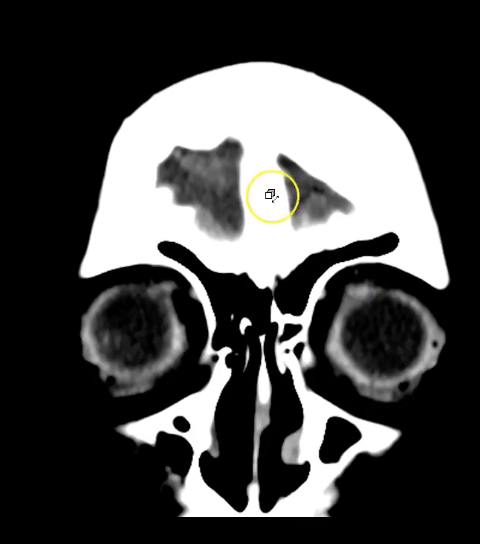

New cards

term image

ethmoid sinuses